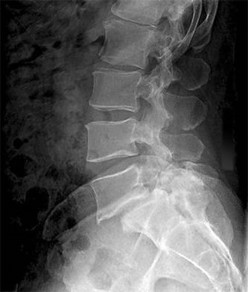

A 35-year-old male construction worker falls 10 feet from scaffolding. He complains of moderate low back pain but has full strength and normal sensation in his lower extremities.

CT imaging shows an L1 burst fracture with 40% loss of anterior vertebral body height and 50% retropulsion into the spinal canal. MRI confirms that the posterior ligamentous complex (PLC) is intact. Based on the Thoracolumbar Injury Classification and Severity (TLICS) score, what is the appropriate score and recommended management?